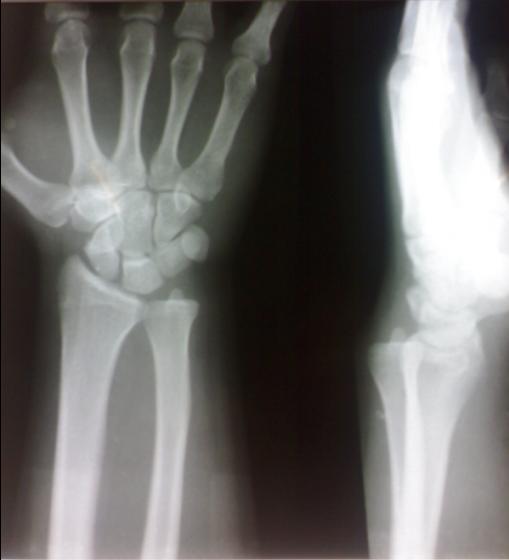

这个是溜冰跌倒手掌撑地造成的 患者5天前打篮球腕部曾受过伤,患者有过习惯性的脱位,余(—)。

远侧桡尺关节半脱位

本人认为所说第一例可考虑尺桡关节脱位,理由是侧位片还算标准,二至五掌骨垂直重叠,如果尺桡骨有内、外旋转,掌骨很难重叠的。

第一例下尺桡关节间隙略宽,可考虑半脱位表现。第二例表现为退变及软组织骨化改变,考虑为陈旧性外伤所致

一、此二例正侧位片投照均不标准,正确的投照体位是肘关节曲约90度,高度最好与肩平齐,前臂尺侧贴紧台面,这样投照出来的位置才是标准的,并且这样投照出来的影像基本不会出现向后半脱位的情况,因为本位置是后半脱位的复位体位。

二、下尺桡关节后半脱位个人认为是不能用x线和ct来诊断的,因为下尺桡关节是个活动度很大的关节,况且还有下尺桡关节不稳定的情况(活动更大,甚至正位间隙都可以超过3-4mm)随不同体位有不同的表现,此二例如果没有看错的话,投照时肘关节是可能是伸直的,而且肘部过于紧张,前臂尺侧没有贴紧台面。

三、这种影像是有特征的,1、尺骨远端向后翘出2、正位像尺骨茎突重叠于尺骨头中部(正常投照时重叠在外侧缘)3、侧位像尺骨茎突亦重叠于中部(正常投照时重叠于后缘)4、正位像下尺桡关节间隙重叠(正常是有完整间隙的)

四、个人认为下尺桡关节半脱位诊断靠临床表现,碰到这种情况又不能确定是否按正确体位投照时要亲自检查患者下尺桡关节,看患者是否有压痛,关节活动度是否大(可用力向前后按压尺骨头),活动时是否有弹响、痛疼,还要嘱患者双侧旋转对比,看患侧尺骨头是否有异常翘起